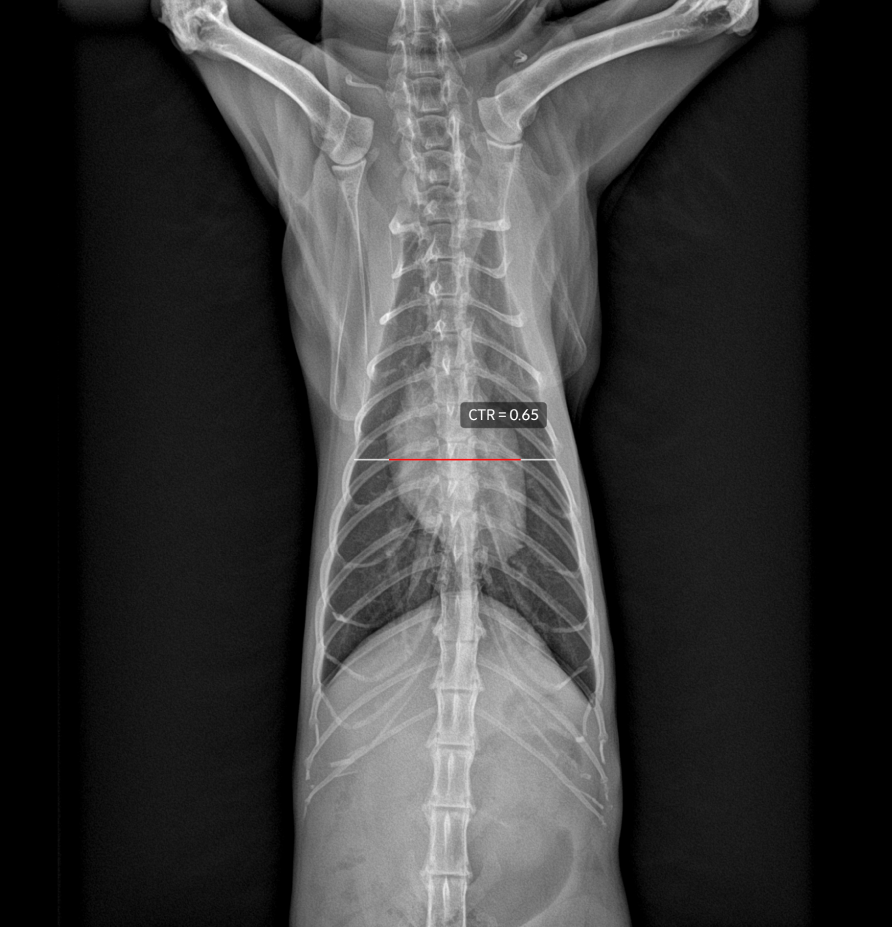

CTR

CTR evaluates overall heart size by comparing the maximum horizontal length of the heart on a VD thoracic radiograph to the maximum thoracic width.